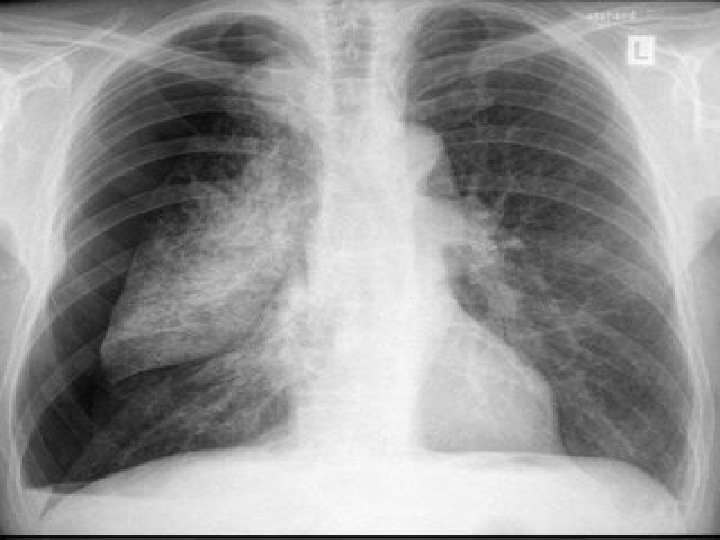

CASE n After initially settling the patient in and continuing on your rounds the RT approaches you and states that the FIO 2 requirements are back up to 100% after a brief period at 50% and hypoxia is becoming an issue. A stat CXR was done.

CASE

CASE n 13) What is your differential for early respiratory failure in the lung transplant? What are the risk factors for early respiratory failure?

Early Respiratory Failure n 1) 2) 3) 4) 5) 6) 7) DDx: Reperfusion injury (55%) Periop cardiovascular(MI, arrhythmia, CHF) /haemorrhagic (36%) Anatomic complications Infectious (bacterial and CMV) Rejection (hyperacute=rare and acute=common) Pneumothorax PE Chatila el. al. Resp failure after lung transplant. Chest 2003; 123: 165 -173.

Early Respiratory Failure n 1) 2) 3) 4) Risk factors: Preop pulmonary htn Rt vent dysfunction Prolonged ischemic time CPB Chatila el. al. Resp failure after lung transplant. Chest 2003; 123: 165 -173.

CASE What is high on your differential for the cause of the abnormality? n The patient requires reintubation, independent lung ventilation and is taken to the OR for repair of his bronchial dehiscence. n Is there any evidence for the outcomes of Lung transplant patients who require readmission to the ICU? n